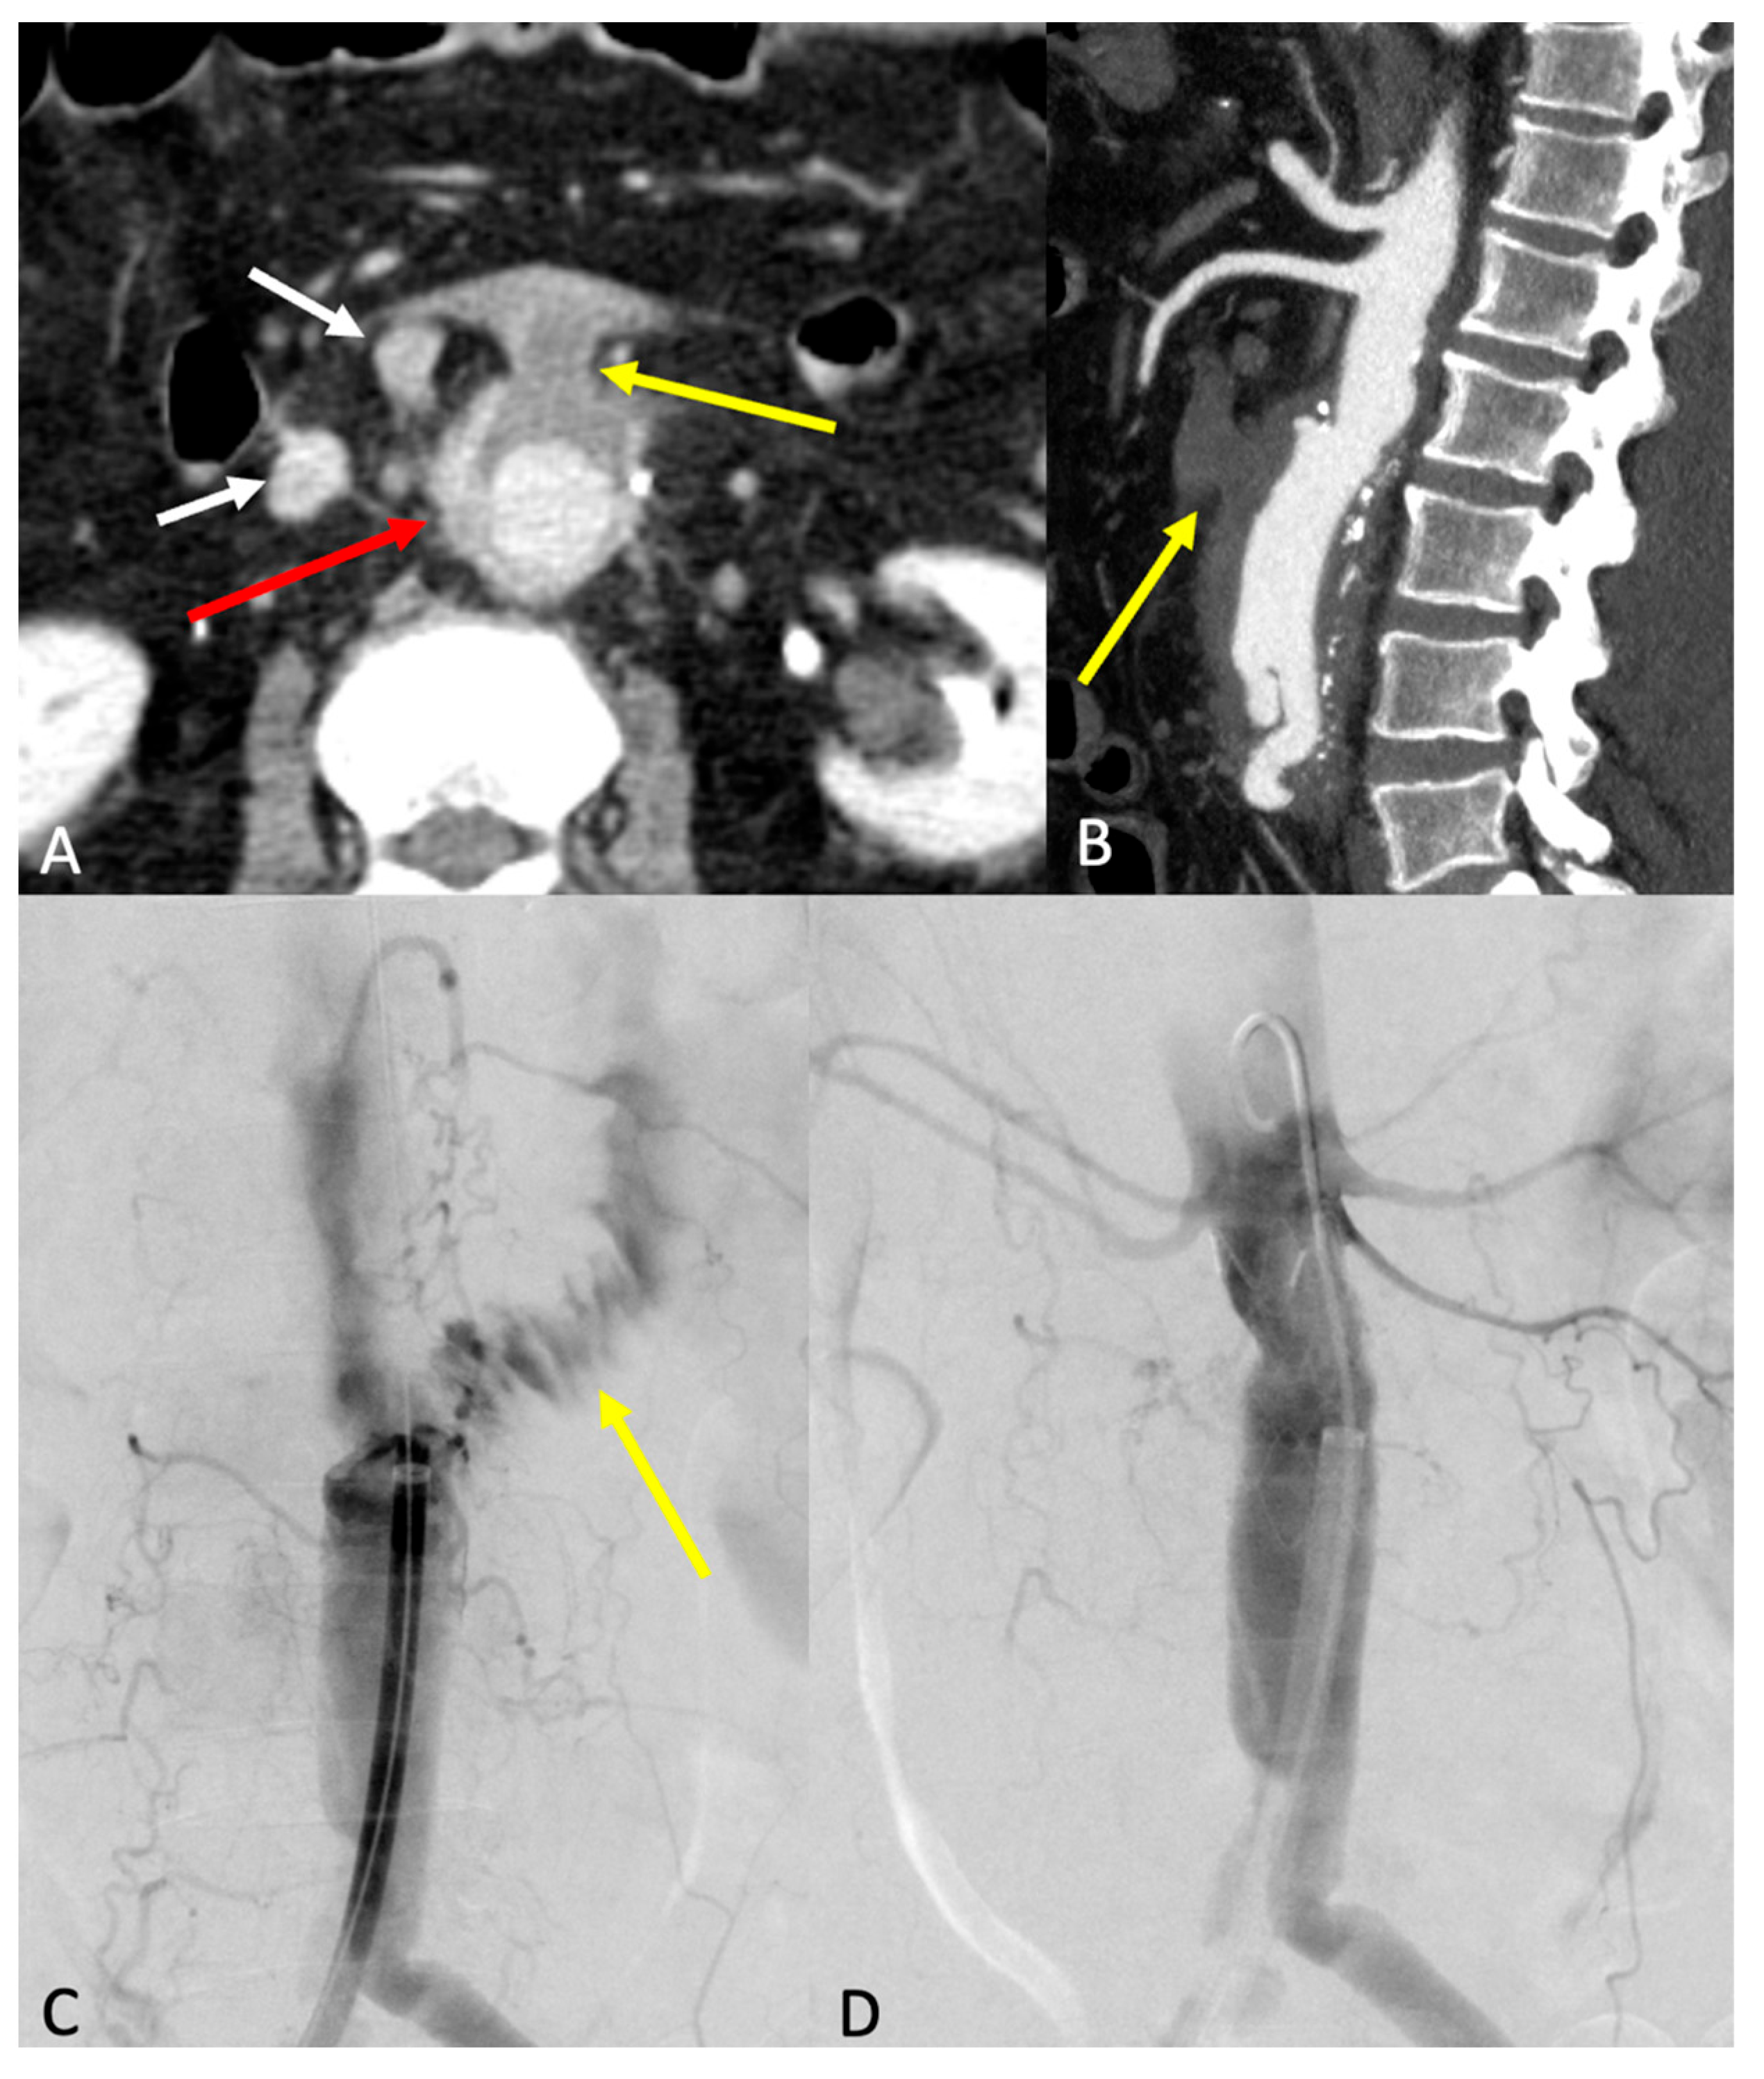

7.3. Endoleak

- Type 1 endoleaks involve direct blood flow into the aneurysm sac due to insufficient seal at the stent graft’s proximal or distal attachment zones. It poses a high risk of rupture and occurs at three possible locations: type 1a, due to inadequate seal at the proximal end; type 1b, due to distal end inadequacy; and type 1c, which occurs at an iliac occluder following aorto-uni-iliac (AUI) repair with femorofemoral crossover graft.

- Type 2 endoleaks: the most common form, arising from collateral vessel backflow, especially from lumbar arteries or the inferior mesenteric artery (IMA). Risk factors include the presence of patent aortic side branches, IMA diameter over 3 mm, patent lumbar arteries (more than three, or over 2 mm in diameter), and anticoagulant use. Embolization of these vessels or non-selective sac embolization can reduce the occurrence of type 2 endoleaks.

- Type 3 endoleaks: these result from stent graft component separation or a tear in the graft fabric. Causes include stent graft migration, inadequate overlap between components (Type 3a), or material fatigue (Type 3b). Component separation can precede the development of an endoleak.

- Stavropoulos, S.W.; Charagundla, S.R. Imaging Techniques for Detection and Management of Endoleaks after Endovascular Aortic Aneurysm Repair. Radiology 2007, 243, 641–655. [Google Scholar] [CrossRef]

- Daye, D.; Walker, T.G. Complications of endovascular aneurysm repair of the thoracic and abdominal aorta: Evaluation and management. Cardiovasc. Diagn. Ther. 2018, 8, S138–S156. [Google Scholar] [CrossRef]